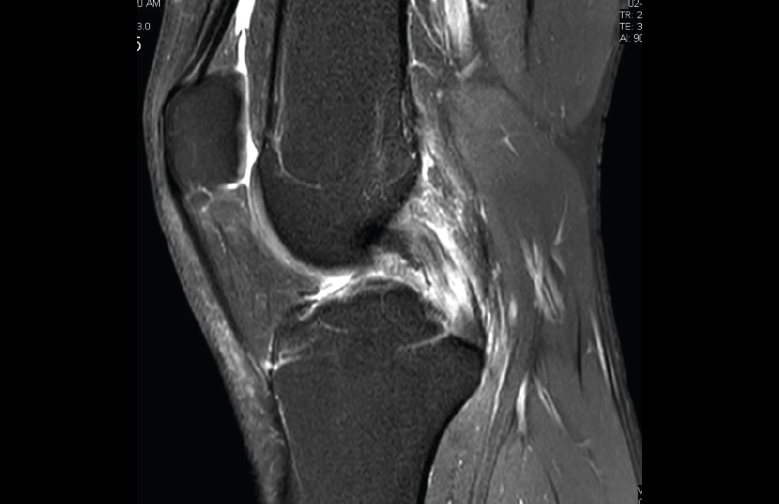

1.2. Ligamentos

Se visualizan como estructuras lineales hipointensas en todas las secuencias.

1.2.1. Ligamentos laterales

Figura 36. Corte de secuencia coronal T2 Fat-Sat: ligamentos colaterales normales.

Ligamento lateral interno (LLI) y ligamento lateral externo (LLE) (Figuras 36, 37, 38 y 39).

1.2.2. Ligamento cruzado anterior (LCA) (Figuras 40, 41, 42, 43 y 44)

Figura 40. Corte de secuencia sagital T2 Fat-Sat de resonancia magnética de rodilla: ligamento cruzado anterior normal.

Figura 41. Cortes de secuencia sagital T2 Fat-Sat de resonancia magnética de rodilla: rotura central del ligamento cruzado anterior.

Figura 42. Cortes de secuencia sagital T2 Fat-Sat: rotura proximal del ligamento cruzado anterior.